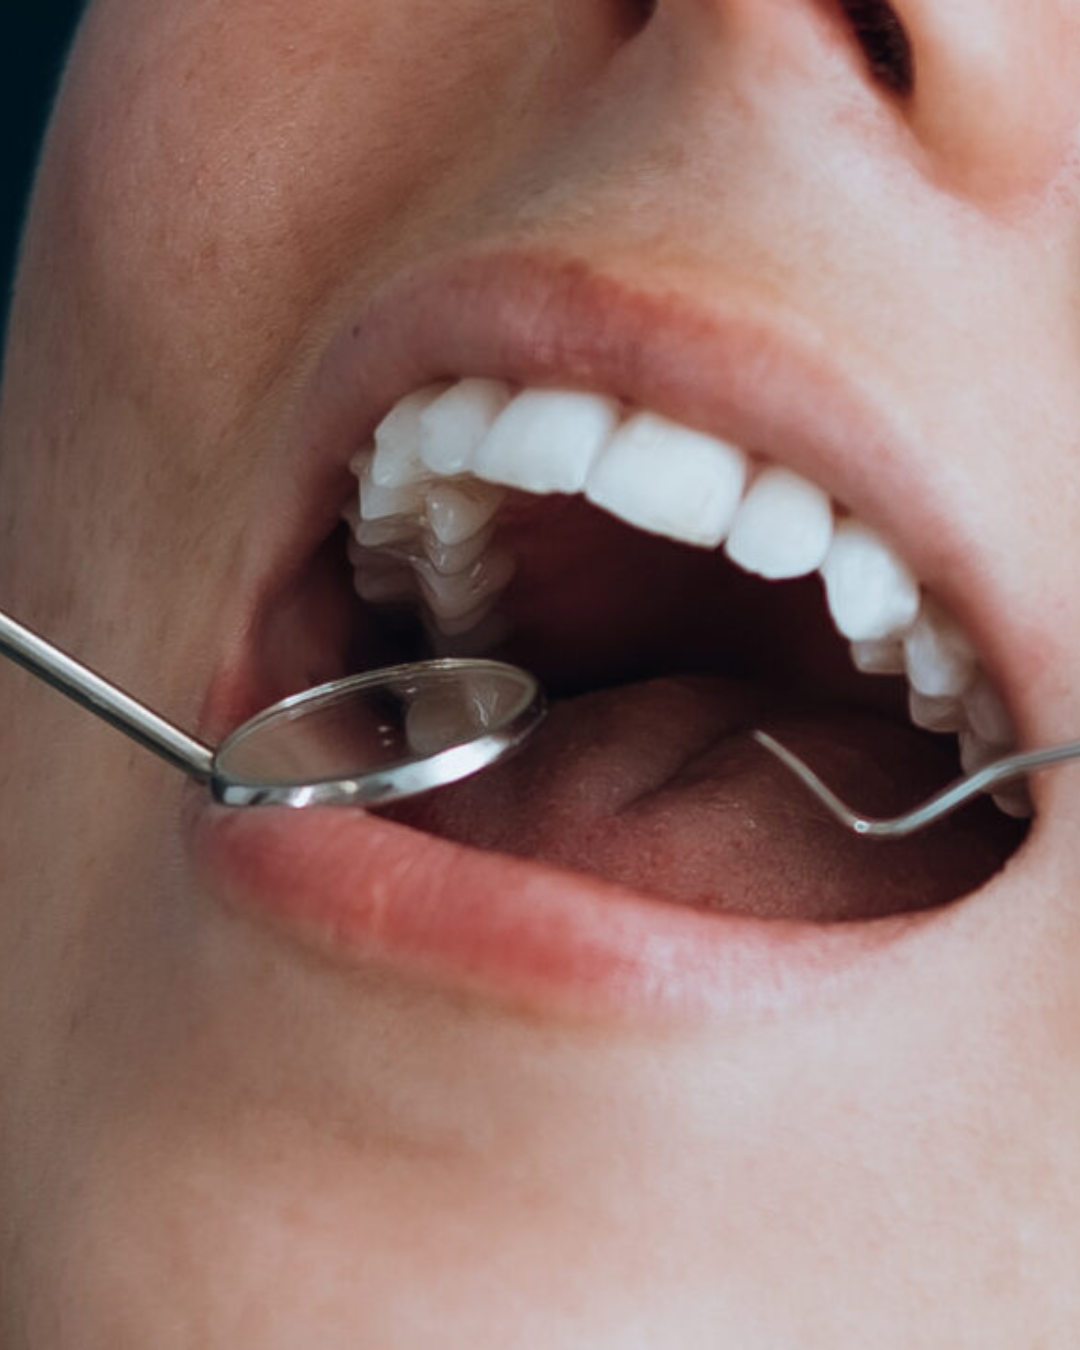

At Infinity Dental Clinic we will do all we can to save your natural teeth. Occasionally there may be unavoidable reasons why this is not possible and an extraction may be required. However, you can be assured we will do all we can to make the process as comfortable as possible.

What to expect from a tooth extraction?